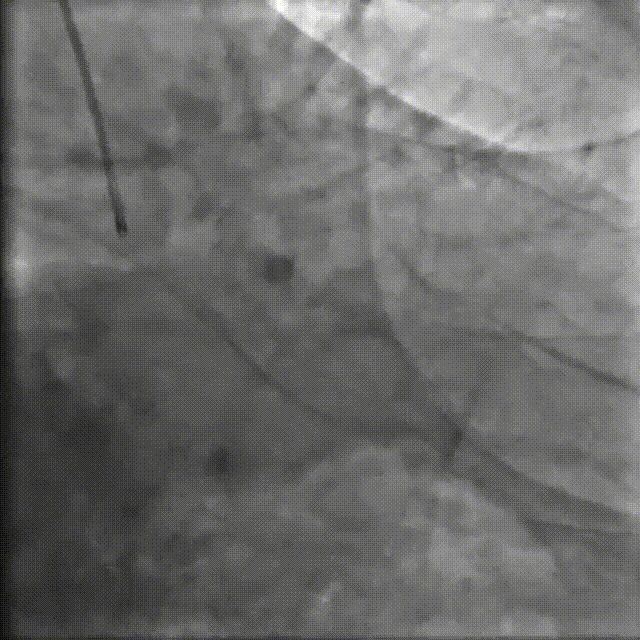

图6.RCA病变处